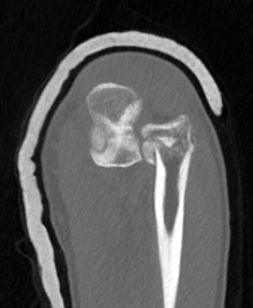

Monteggia variant

Definition

Elbow dislocation + olecranon fracture + radial head/neck fracture +/- coronoid fracture